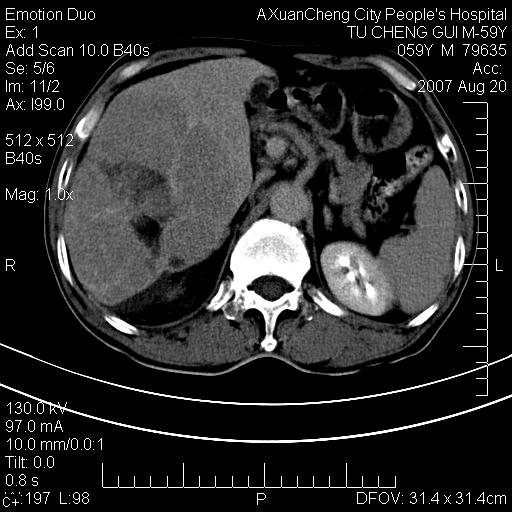

标题: CT9451:M59Y,肝脏占位

肝区涨痛一周,肝功能转氨酶均轻度增高

增强

典型的肝癌(巨块型)、腹水,有供血动脉。

巨块性肝癌!(平扫不均匀低密度,增强方式典型的快进快出)

典型的快进快出,动脉期可见肿瘤组织的供血动脉,肝下间隙可见条带状水样低密度区,符合原发性肝癌的ct表现。可以查一个afp >300有意义

患者有肝硬化,平扫病灶呈不均性低密度,增强呈快尽快出表现,内见更低密度灶,静脉期延迟期呈低密度符合肝癌表现,内低密度为坏死改变并少量胸腹水。

动脉期肝右动脉粗细不均,走行有点迂曲,门脉期门脉右支有点受侵,并且中心有坏死,呈快进快出,符合肝癌

典型肝癌ct表现(肝右叶肿块密度不均,增强典型快进快出,内部有液化坏死,可能有脂肪变性)。

肝右叶巨块型肝癌伴少量腹水.双侧少量胸腔积液.